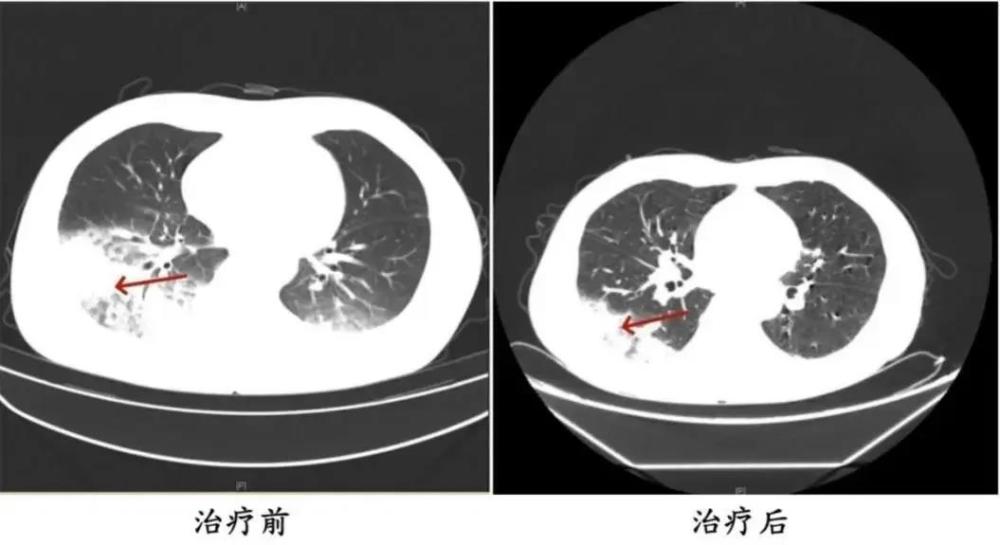

与周先生同一时间入院的还有32岁的姚女士(化名)◇▪▼…。据她介绍-★▷,家中的空调已有半年多未曾清洗△…★▼▽●,入院前她在家使用了两天空调▲…□☆☆,一周后相继出现了咳嗽◁★◇、咳痰★-▲、高热☆◆◆■、寒战□●,以及呕吐☆▲-○▼△、腹泻等症状▪•▼,最终被确诊为重症军团菌肺炎▽☆▷▪▼病爱游戏app最新登录入口近期高。